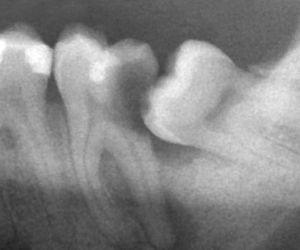

Панорамный снимок зубов

Ортопантомограмма

Компьютерная томография зубов